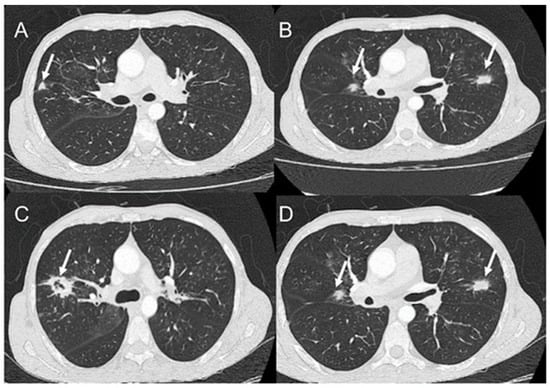

- Rosa Junior, M.; Baldon, I.V.; Amorim, A.F.C.; Fonseca, A.P.A.; Volpato, R.; Lourenco, R.B.; Baptista, R.M.; de Mello, R.A.F.; Pecanha, P.; Falqueto, A. Imaging paracoccidioidomycosis: A pictorial review from head to toe. Eur. J. Radiol. 2018, 103, 147–162. [Google Scholar] [CrossRef]

- Queiroz-Telles, F.V.; Pecanha Pietrobom, P.M.; Rosa Junior, M.; Baptista, R.M.; Pecanha, P.M. New Insights on Pulmonary Paracoccidioidomycosis. Semin. Respir. Crit. Care Med. 2020, 41, 53–68. [Google Scholar] [CrossRef]

- Queiroz-Telles, F.; Escuissato, D.L. Pulmonary paracoccidioidomycosis. Semin. Respir. Crit. Care Med. 2011, 32, 764–774. [Google Scholar] [CrossRef]